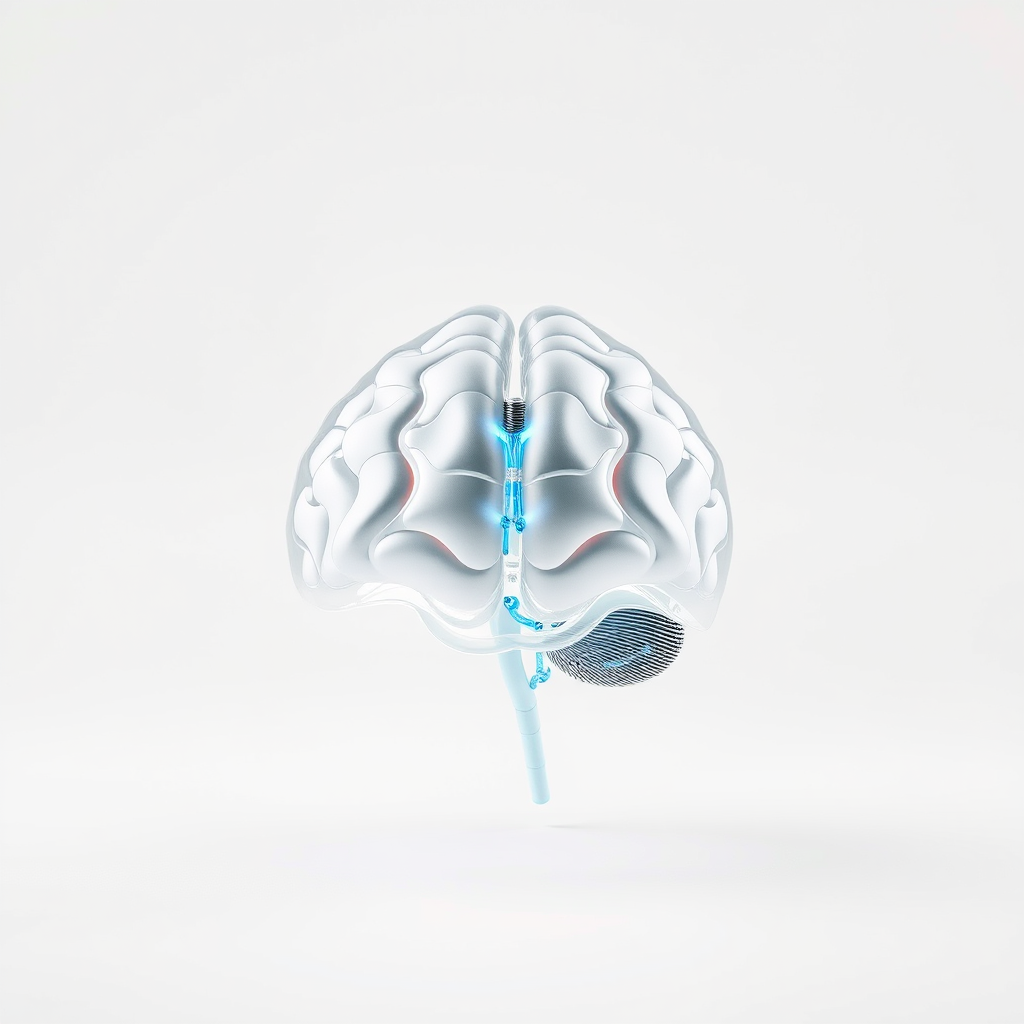

Tratamento para Transtornos Neurocognitivos

O tratamento para transtornos neurocognitivos é uma área essencial da saúde mental.

Este campo abrange uma variedade de condições que afetam as funções cognitivas e comportamentais dos indivíduos.

Os transtornos neurocognitivos podem surgir devido a diversas causas, incluindo lesões cerebrais, doenças degenerativas e condições psiquiátricas.

O que são Transtornos Neurocognitivos?

Os transtornos neurocognitivos são condições que afetam a capacidade de pensar, lembrar e se comportar de maneira adequada.